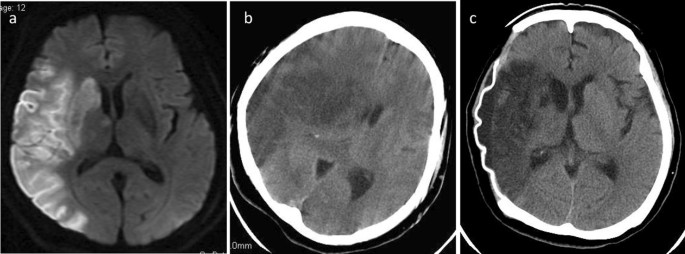

1. 신속한 평가 및 진단: 뇌경색 초기증상과 징후를 신속하게 인식하는 것은 적시에 개입하고 환자 결과를 개선하는 데 필수적입니다. 의료 전문가는 NIHSS(National Institutes of Health Stroke Scale)와 같은 도구를 사용하여 잠재적인 뇌경색 환자를 신속하게 평가하고 컴퓨터 단층 촬영(CT) 스캔 또는 자기 공명 영상(MRI)을 포함한 진단 테스트를 시작하여 진단을 확인하고 유형을 결정해야 합니다.

2. 즉각적인 치료: 뇌경색이 진단되면 뇌 손상을 최소화하기 위해 가능한 한 빨리 치료를 시작해야 합니다. 특정 치료는 뇌출혈 유형에 따라 다릅니다(허혈성 또는 출혈성) 다음과 같이 분류할 수 있습니다.

• 허혈성 뇌졸중(혈전이 뇌로 가는 혈류를 차단하여 발생)의 경우 증상이 시작된 후 처음 4.5시간 이내에 조직 플라스미노겐 활성화제(tPA)와 같은 혈전 용해 약물을 투여하면 결과를 크게 개선할 수 있습니다. 경우에 따라 기계적 혈전 제거술과 같은 혈관 내 절차를 수행하여 혈전을 제거하고 혈류를 회복할 수도 있습니다.

• 출혈성 뇌졸중(뇌 내 출혈로 인해 발생)의 치료는 출혈 조절, 두개골 내 압력 감소, 근본 원인 해결에 중점을 둡니다. 여기에는 혈압을 조절하거나 항응고를 역전시키거나 뇌 부종을 줄이기 위한 약물이 포함될 수 있습니다. 어떤 경우에는 혈액을 제거하거나 손상된 혈관을 복구하기 위해 외과적 개입이 필요할 수 있습니다.